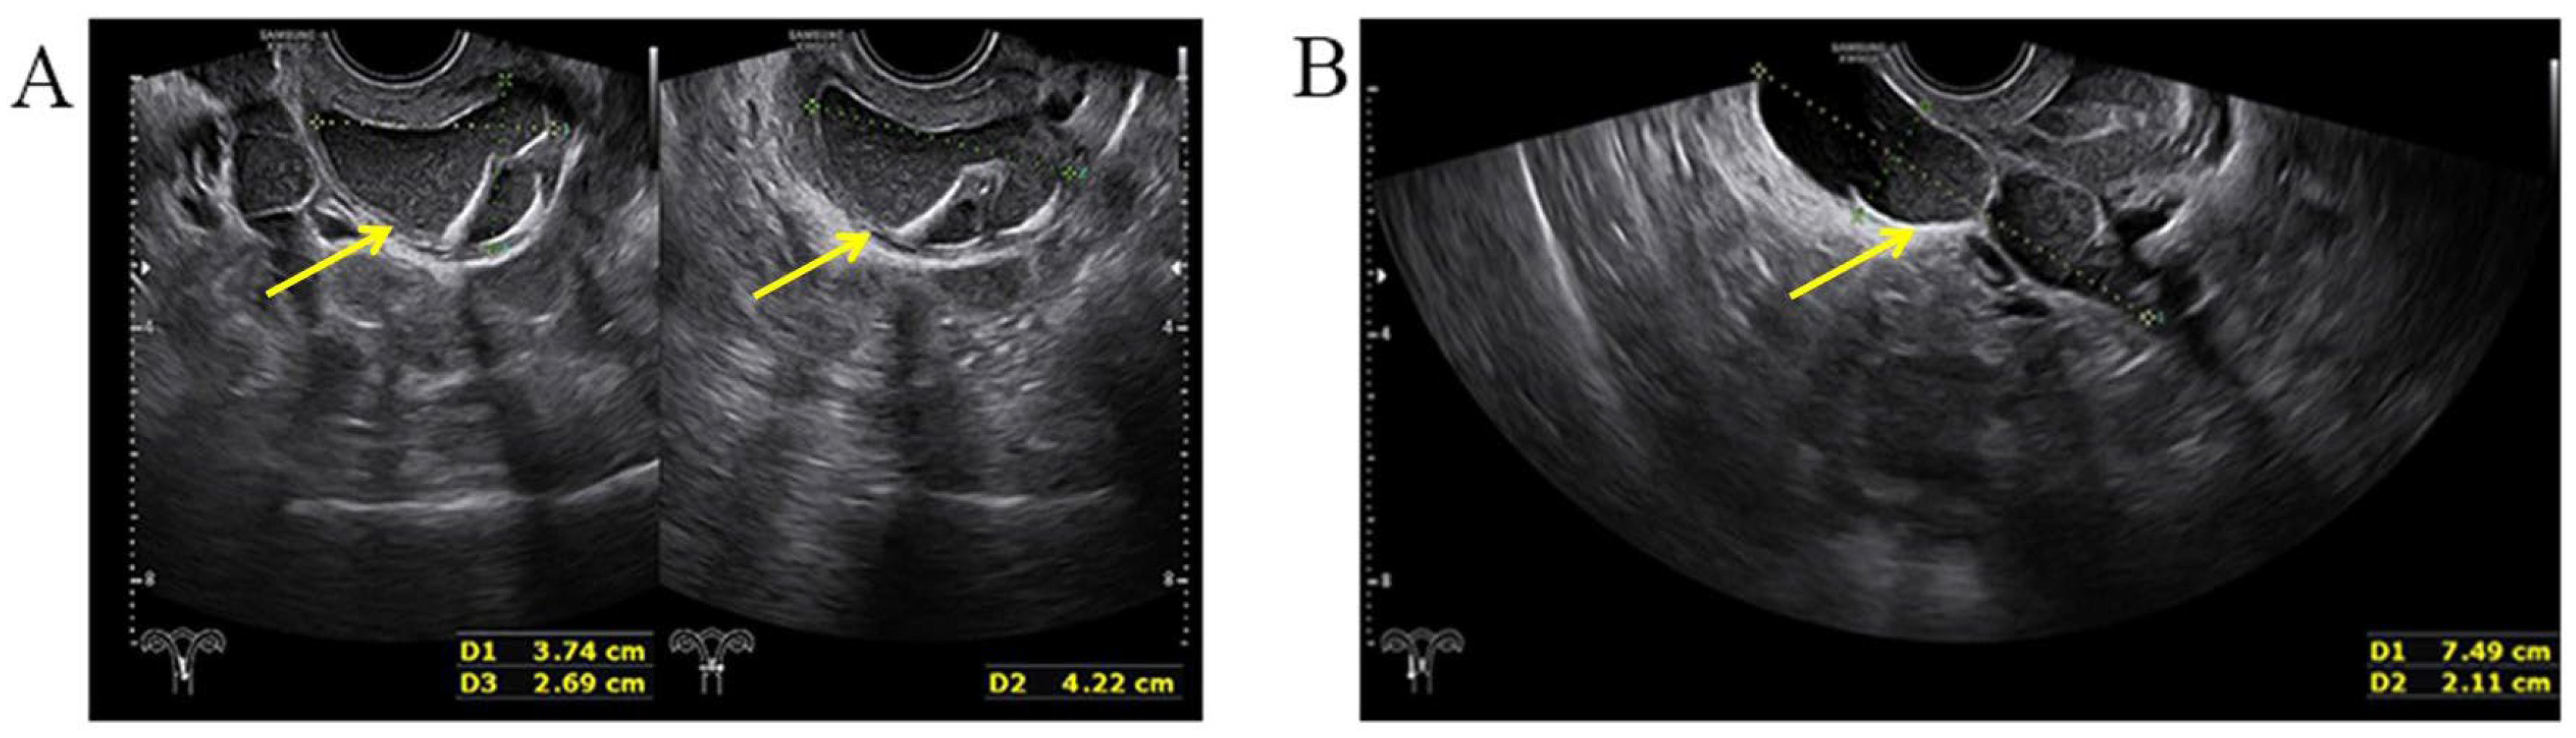

A three-dimensional transvaginal ultrasound revealed adenomyosis and a septate uterus (Figure 1). Two cystic masses with thick internal fluid measuring 3.7 × 4.2 × 2.7 cm (Figure 1A) and 7.5 × 3.1 × 2.1 cm (Figure 1B) were seen on the right side of the uterus, respectively. These cystic masses were considered to be a hydroureter with vaginal fistula. A urinary tract ultrasound revealed the absence of a right kidney, as well as a dilated right ureter measuring 11.1 × 1.8 cm with an ectopic opening into the right vagina (Figure 2A). A computed tomography urography (CTU) revealed the absence of the right kidney (Figure 2B). A pelvic MRI showed a cystic mass considered to be a mesonephric cyst on the right side of the pelvis, bladder, and urethra (Figure 3A). A complete septate uterus with multiple fibroids was also found (Figure 3B). The creatinine concentration of the fluid inside the pelvic cyst was measured to be 157 nmol/L via transvaginal aspiration (Figure 4).

Figure 1.

Three−dimensional transvaginal ultrasound. (A) Transvaginal ultrasound demonstrated a cystic mass with thick internal fluid measuring 3.7 × 4.2 × 2.7 cm on the right side of the cervix. (B) Transvaginal ultrasound demonstrating a cystic mass measuring 7.5 × 3.1× 2.1 cm was seen next to the right side of uterus and its opening into right vaginal wall.